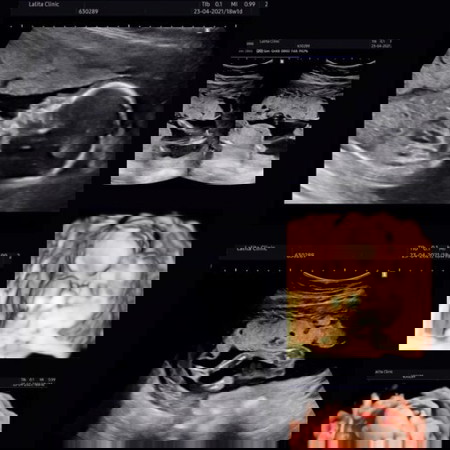

อยากทราบว่าแม่ที่คลอดน้องเดือนเมษาน้องดิ้นกันบ้างกรือยังค่ะ ส่วนแม่บ้านนี้ยังตอดอยู่เลยเป็นเพราะแม่นั้นอ้วนตั้งแต่ก่อนท้อง มาแชร์ภาพท้องแม่และลูกในครรภ์กันจ้า กำหนดคลอด 23เมษา วันนี้ 19w พอดี